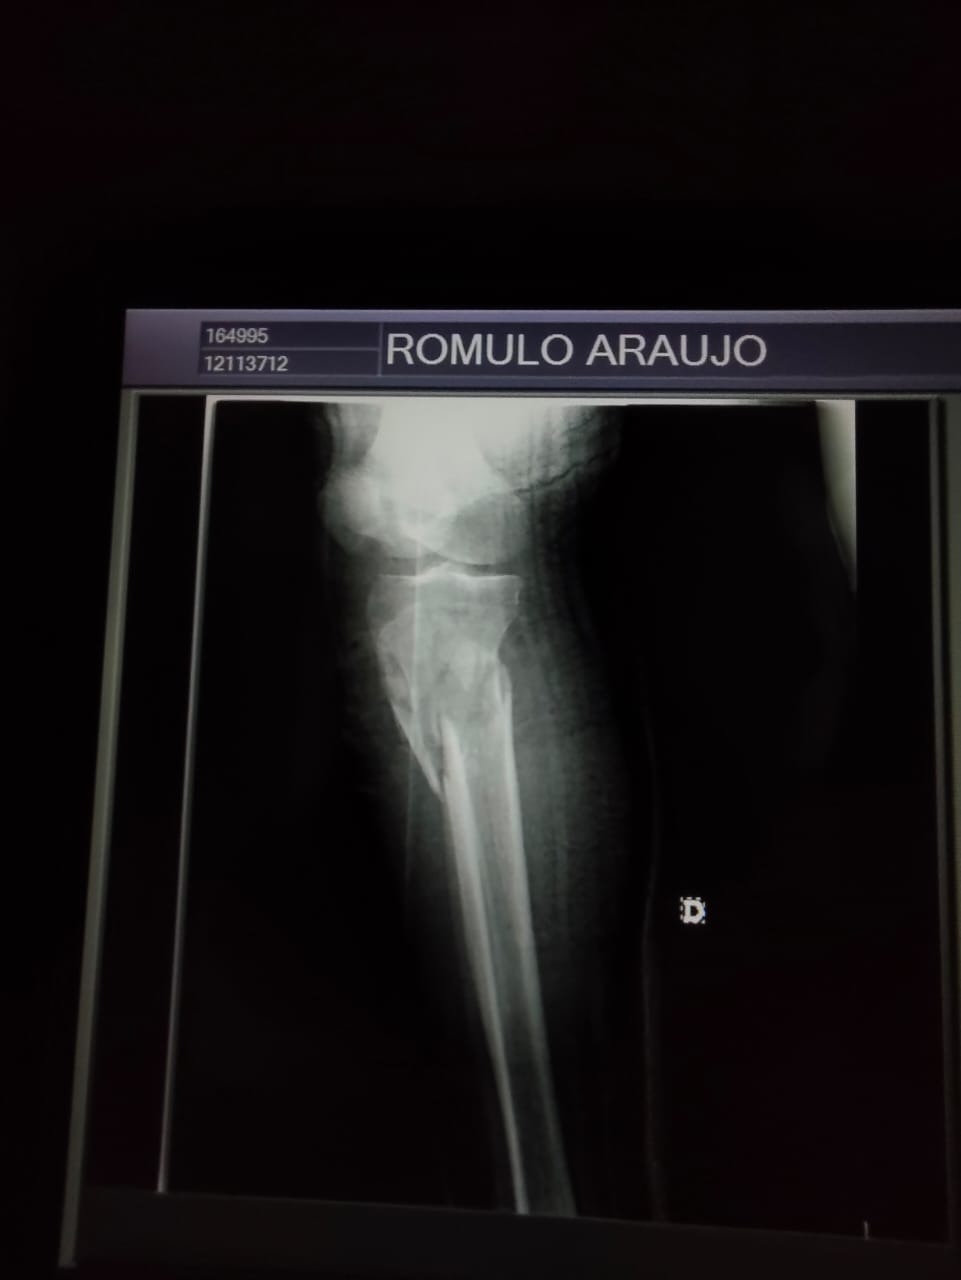

Fractura de fémur

Fractura de tibia

Rodilla gravemente lesionada

Problemas en la cadera

Necesita una cirugía urgente para reconstruir su pierna y evitar complicaciones permanentes. Sin esta operación, corre el riesgo de perder movilidad y no poder volver a caminar con normalidad.